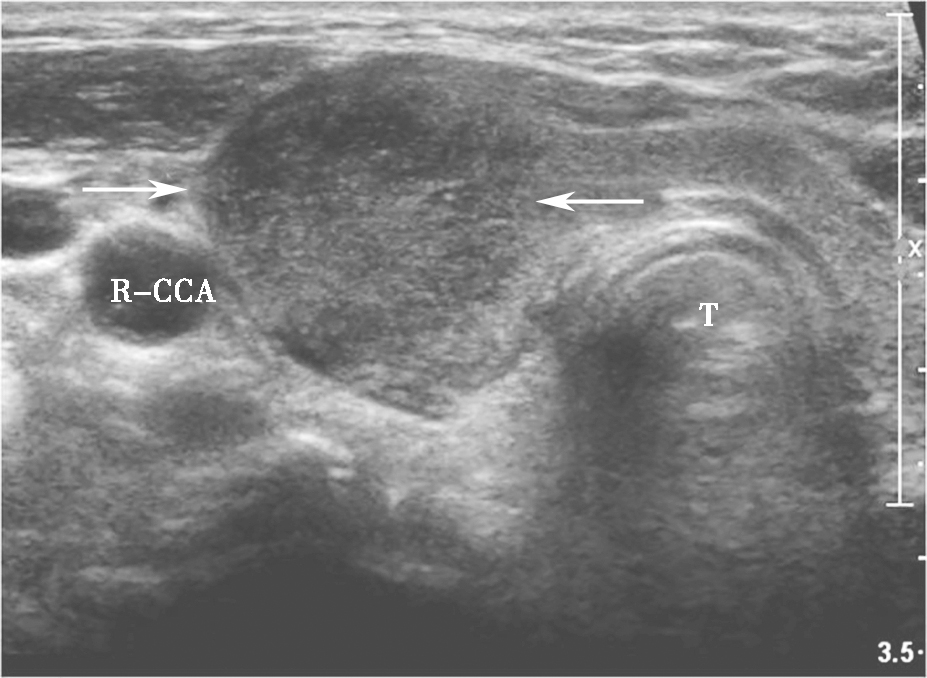

(六)亚急性甲状腺性炎

图5颈部正中偏右侧横切面:甲状腺右叶饱满,可见片状低回声,边界模糊(箭头所示)R-CCA:右侧颈总动脉,T:气管